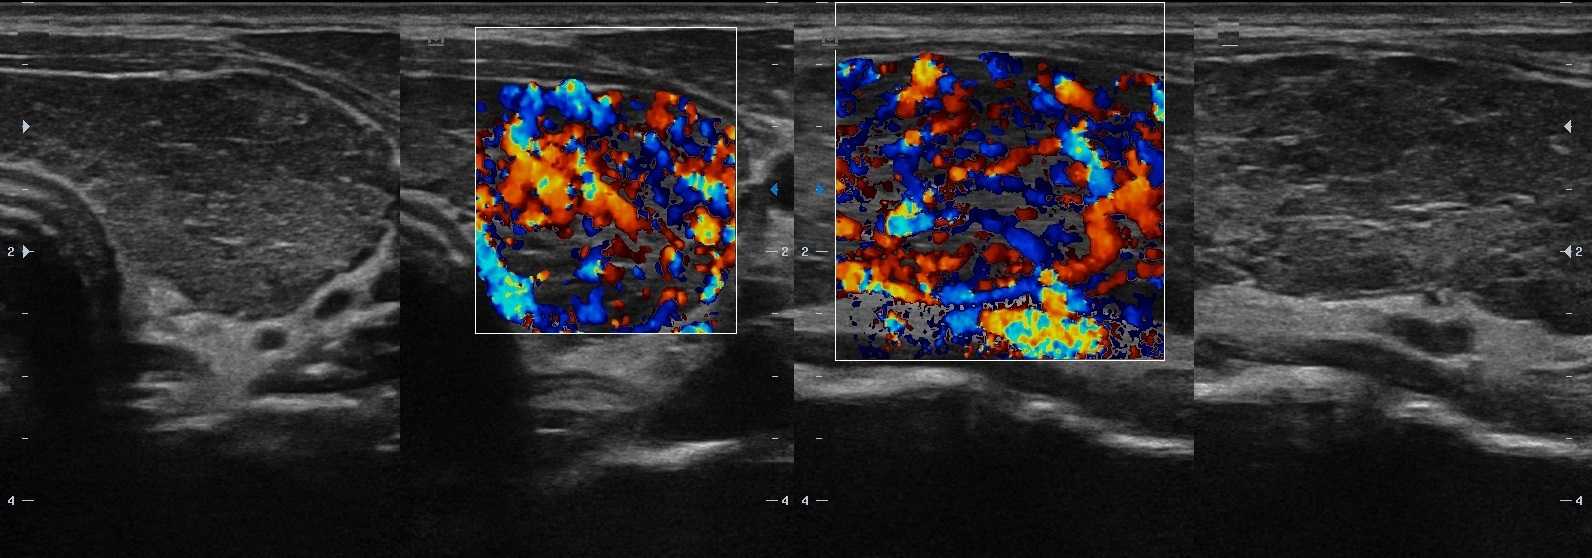

Рисунок. Пациент с гипотиреозом и антитиреоидными антителами. На УЗИ щитовидная железа диффузно увеличена; контур волнистый; на фоне нормальной паренхимы в большом количестве гипоэхогенные очаги (3-5 мм) с четким контуром без «гало». Заключение: АИТ, гипертрофическая форма.

Рисунок. Пациент с гипертиреозом и антитиреоидными антителами. На УЗИ щитовидная железа диффузно увеличена; на фоне общего снижения эхогенности определяются гипоэхогенные включения (2-4 мм) и линейные гиперэхогенные структуры; кровоток заметно усилен. Заключение: АИТ, гипертрофическая форма.